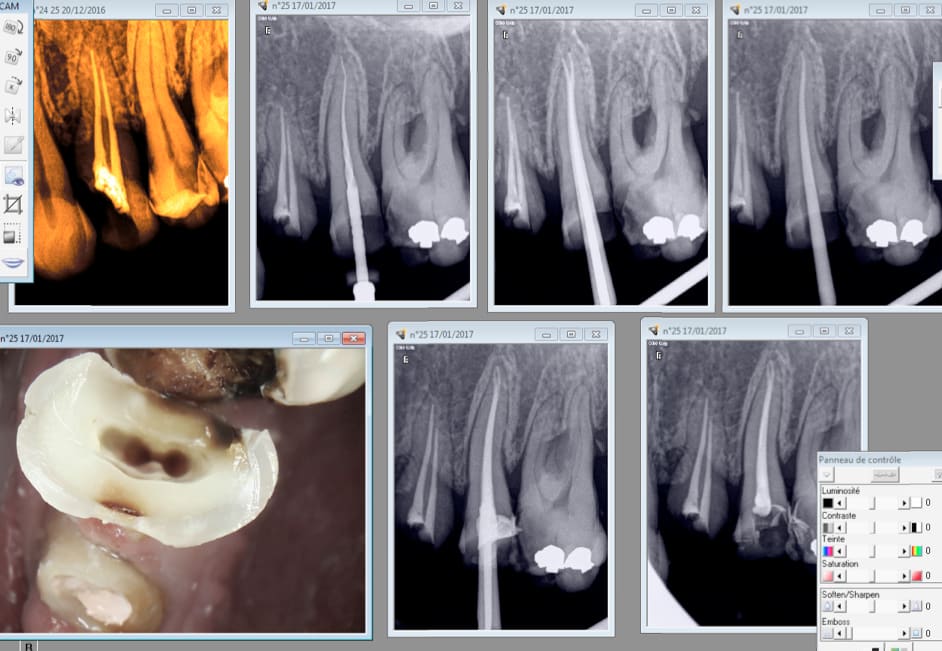

Voici en pièce jointe typiquement les images de dépassements que jai régulièrement. Jai pourtant suivi les instructions du commercial dentsply. Je ne pense pas qu'il s'agisse de gutta étant donné la fine épaisseur... bon je pense que je vais finir pas revenir à la gutta classique ... :/

Img 4453 kwxc1a - Eugenol

Si tu sur prépares ca fuse.

Avec un monocone tu ajustes si ca dépasse un peu puis tu le scelles et tu y fous un coup de mac spadden.

17/01/2017 à 11h58

Mono cone scellé et condensé au mac spadden. Te fais pas chier.

Essayage du cone si ca dépasse tu le coupes, puis tu le scelles puis tu le condenses.

Je ne pense pas que le suralésage soit la cause ici.

J'utilise depuis longtemps le thermafill et j'ai de temps à autre les mêmes images.

La pression au moment de l'insertion est très importante et même en insérant trèèès lentement on a souvent des dépassement de ciment qui lui est très fluide.